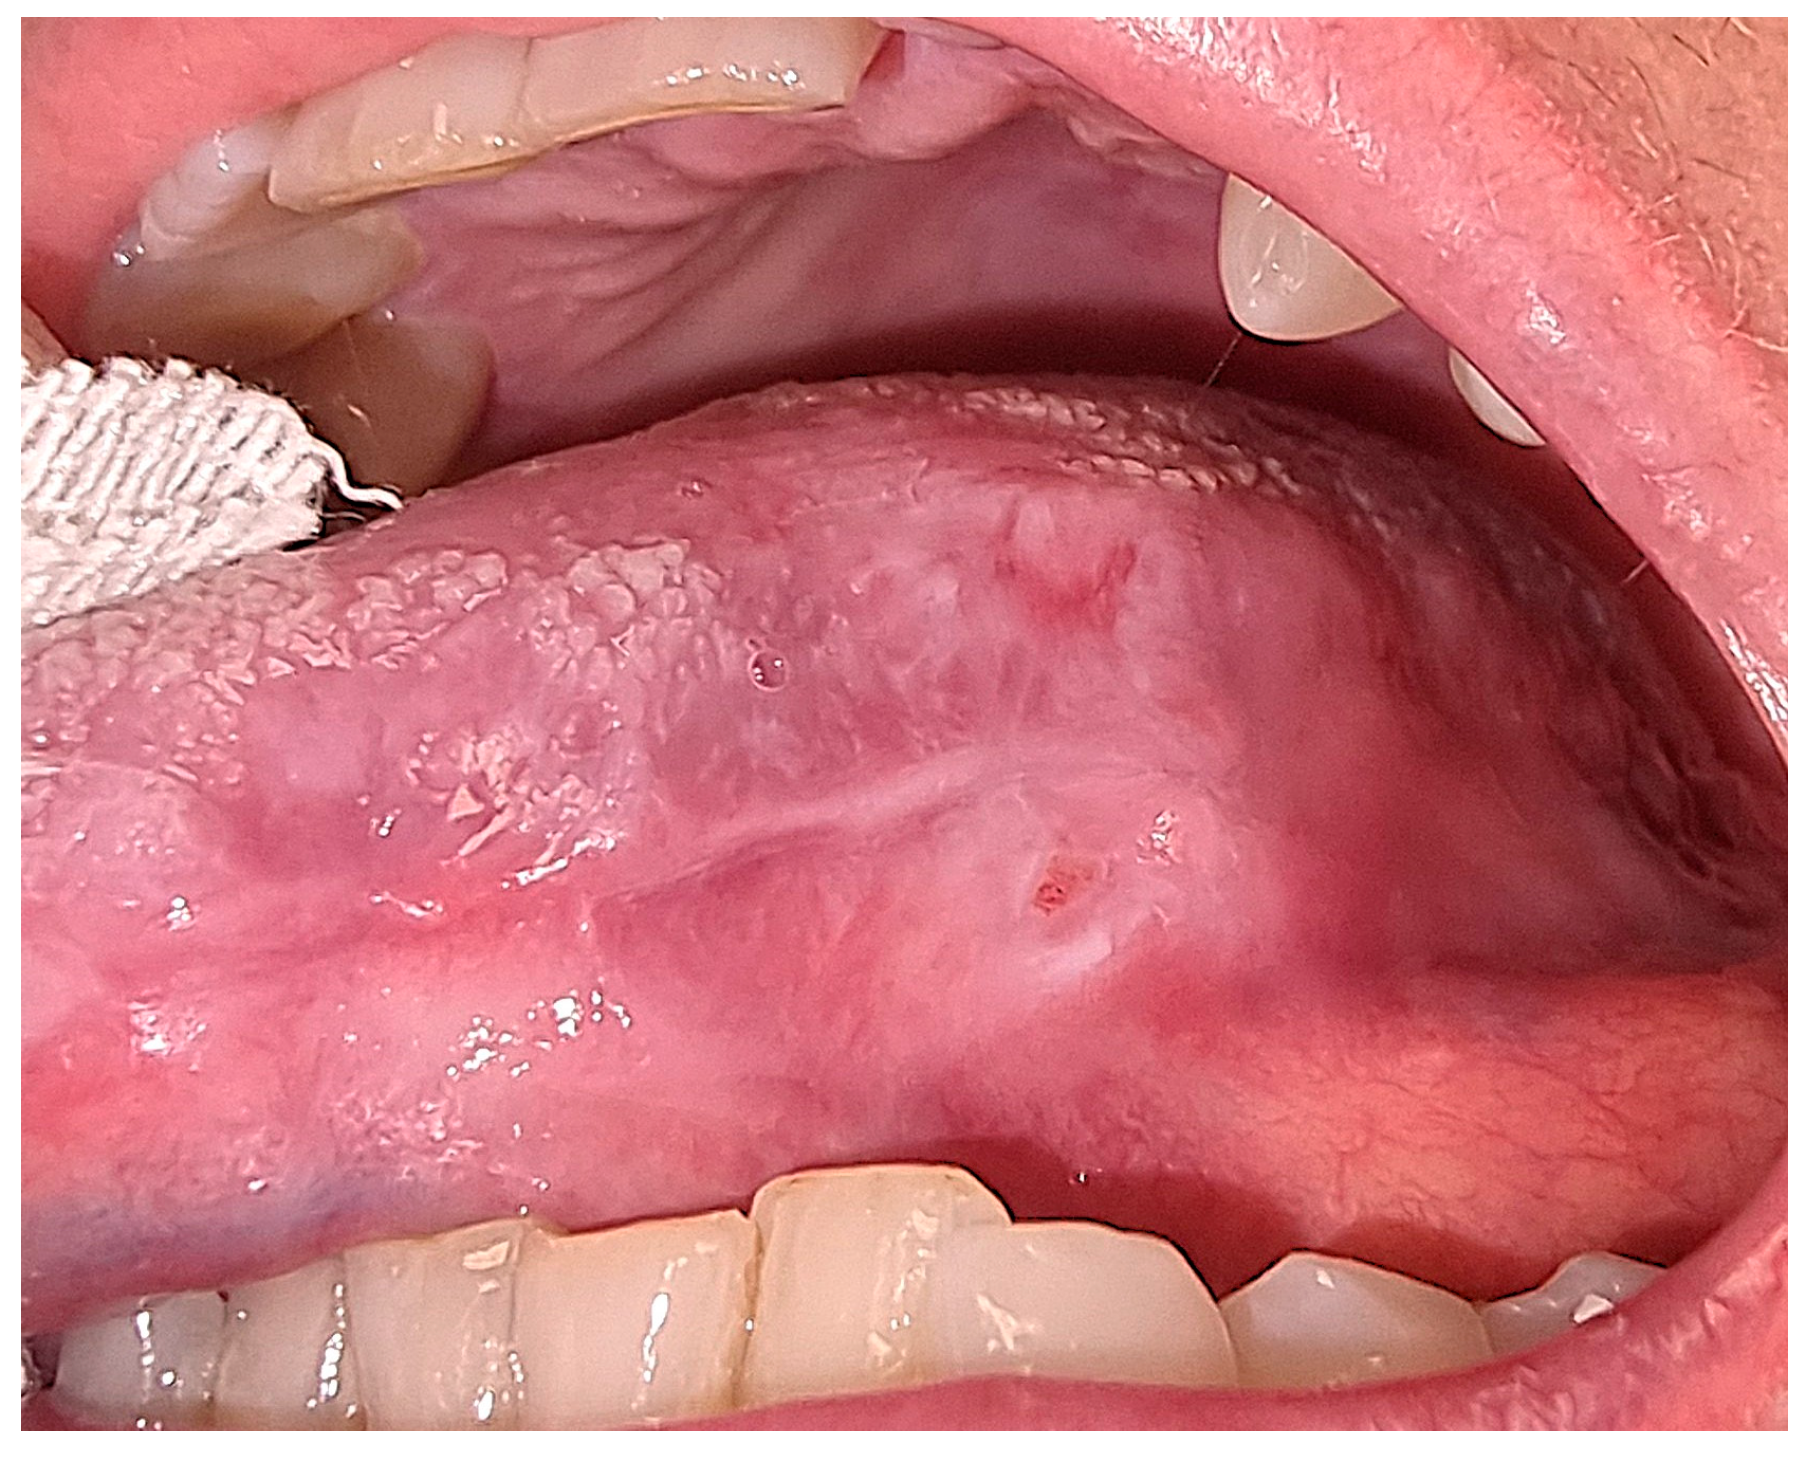

3. Results